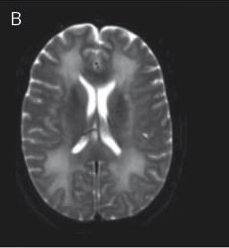

DWI MRI: Bilateral white matter hyperintensities.